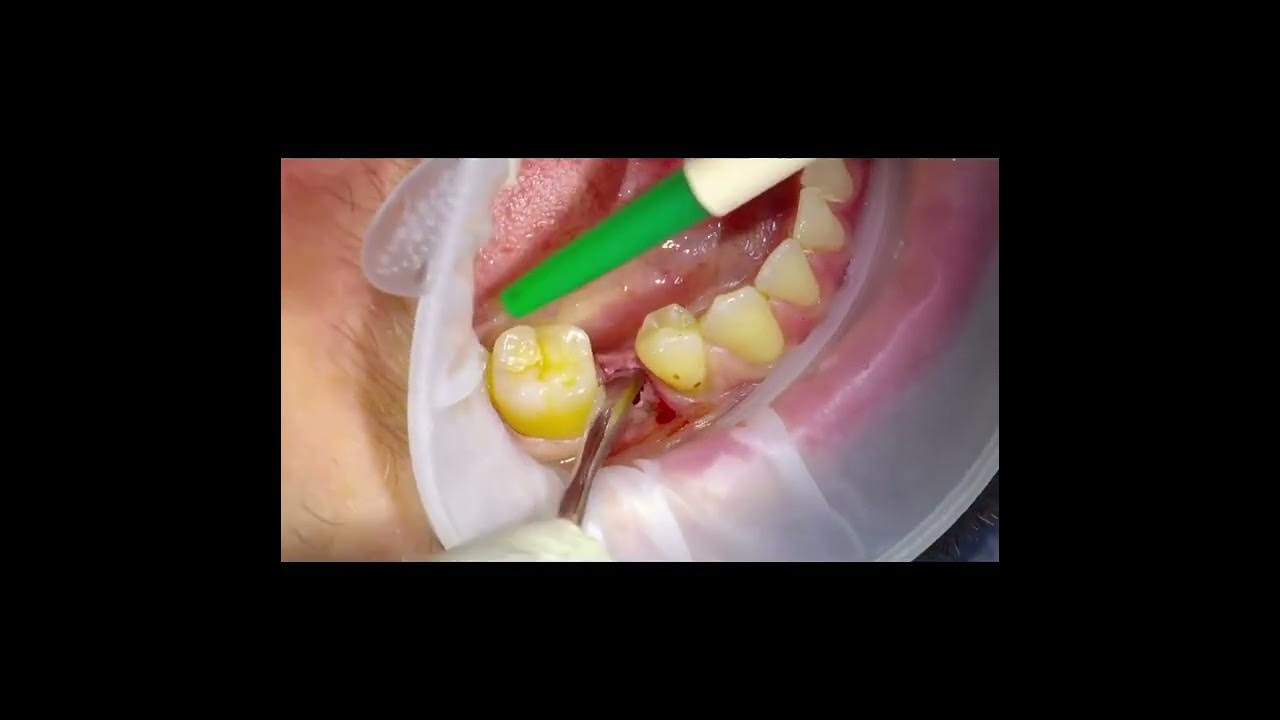

Dental Implant Surgery Step by Step (2/7) Extraction and Ridge Dental Implants Procedure Youtube All you need to know about getting dental implants and how ethoss bone grafting material helps you get the best results.you can. In this video we will review a dental implant procedure step by step. How is a dental implant inserted step by step and what advantages does it have compared to a dental bridge | tooth implant,. Most of. Dental Implants Procedure Youtube.